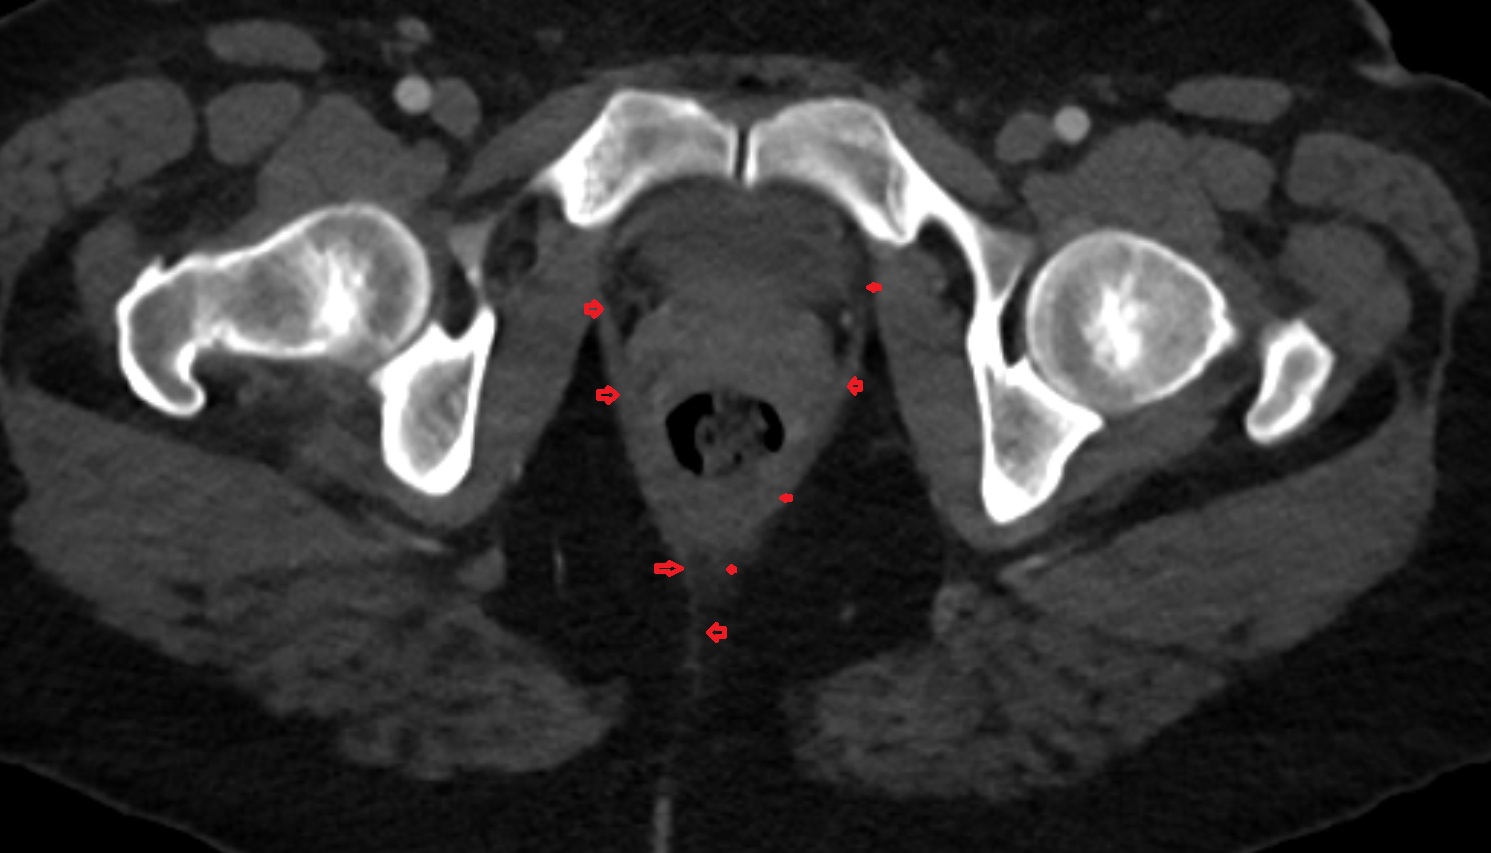

- Peripheral zone of prostate

- Anterior Fibromuscular Stroma of prostate

- Central zone of prostate

- Transitional zone of prostate